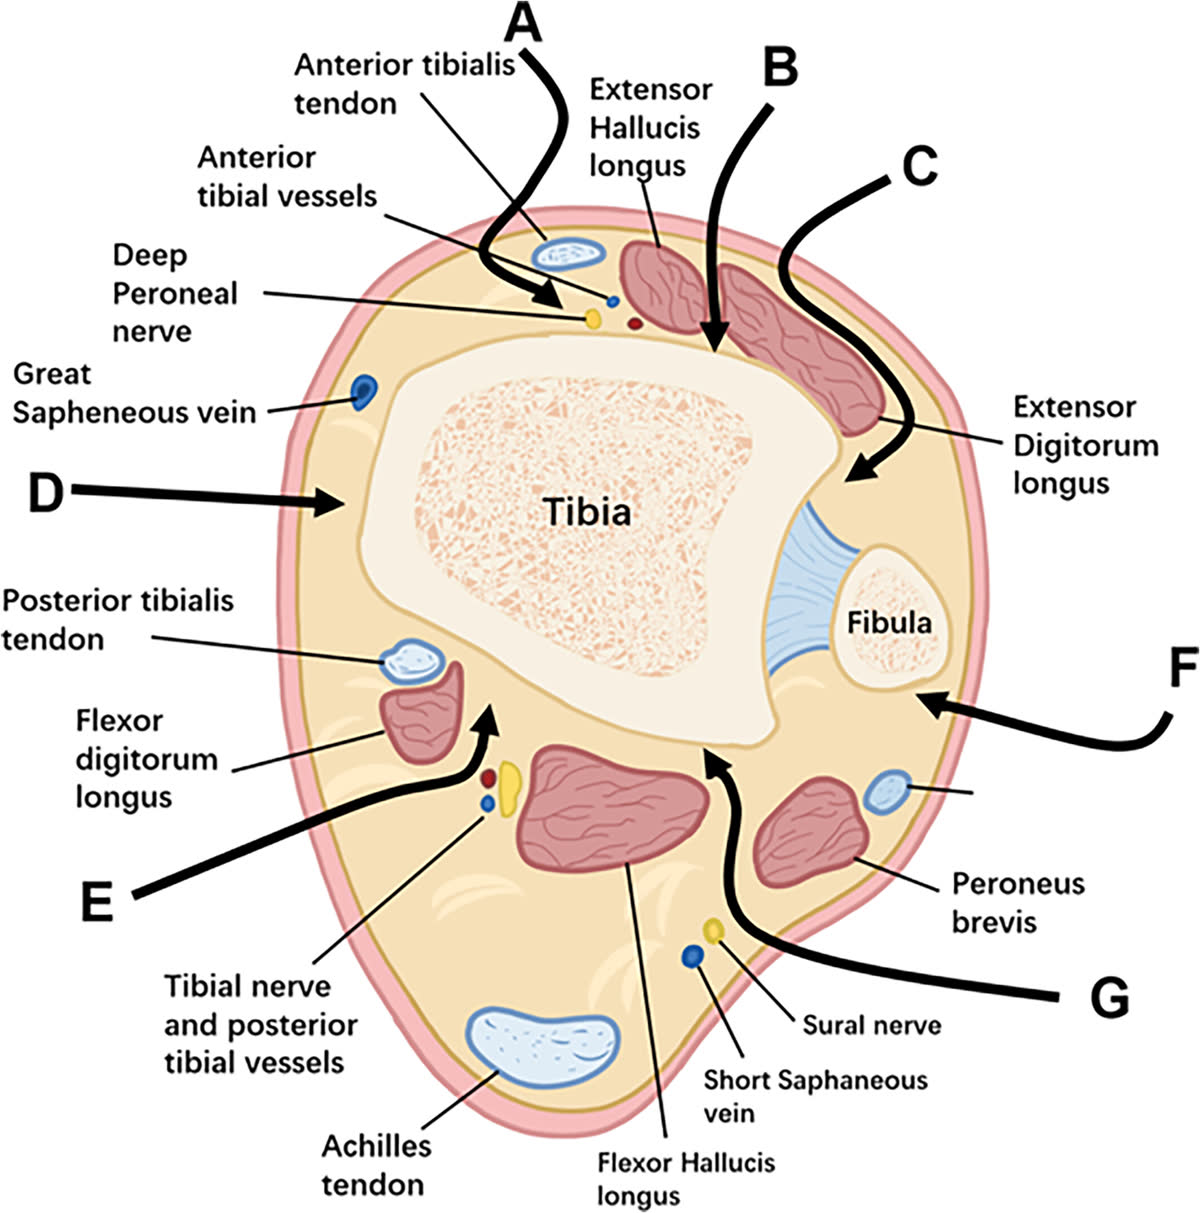

Топография хирургических коридоров

Переднелатеральный коридор (по латеральному краю длинного разгибателя пальцев и передним краем малоберцовой кости): риск повреждения поверхностного малоберцового нерва, который расположен в поверхностном слое до фасции голени. Сосудисто-нервный пучок (a. tibialis anterior, n. peroneus profundus) располагается в глубоком слое, на уровне голеностопного сустава, между сухожилием длинного сгибателя первого пальца и длинным сгибателем пальцев.

Переднемедиальный коридор (между сухожилием передней большеберцовой мышцы и медиальной лодыжкой): должна выполняться минимальная диссекция мягких тканей. Риск повреждения v. saphena magna и n. saphenus, располагающихся впереди медиальной лодыжки в поверхностном слое.

Заднелатеральный коридор (между малоберцовыми мышцами и длинным сгибателем большого пальца): безопасная зона при условии работы латеральнее длинного сгибателя первого пальца (FHL). Риск — n. suralis при мобилизации малоберцовых мышц. Глубокий сосудисто-нервный пучок (a. tibialis posterior, n. tibialis) располагается медиальнее сухожилия длинного сгибателя первого пальца.

Заднемедиальный коридор (между задней большеберцовой мышцей и длинным сгибателем пальцев): обеспечивает доступ к заднемедиальным фрагментам и тарзальному каналу. Риск — задний сосудисто-нервный пучок располагается латеральнее этого интервала.

Хирургические доступы

Переднелатеральный доступ

- Показания: переднелатеральный фрагмент (Chaput/Tillaux-Chaput), переднелатеральная колонна

- Разрез между сухожилиями длинного разгибателя пальцев и латеральной лодыжкой

- Переднелатеральный фрагмент присутствует при большинстве переломов с вовлечением суставной поверхности дистального отдела большеберцовой кости [Rammelt et al., JBJS Am, 2022]

Переднемедиальный доступ

- Показания: медиальная колонна, центральная импакция суставной поверхности

- Разрез между сухожилием передней большеберцовой мышцы и медиальной лодыжкой

Заднелатеральный доступ (положение на животе)

- Показания: задняя колонна (фрагмент Volkmann), заднелатеральный вариант пилона

- Между сухожилиями малоберцовых мышц и длинного сгибателя первого пальца

- Позволяет напрямую визуализировать заднюю суставную поверхность

Заднемедиальный доступ

- Показания: медиальная колонна, заднемедиальные фрагменты

- Между сухожилиями задней большеберцовой мышцы и длинного сгибателя пальцев

Принципы выбора доступа

Доступ определяется стратегией репозиции, а не выбором импланта. Основа планирования — аксиальные КТ-срезы на 1 см выше суставной щели голеностопного сустава.

При полных внутрисуставных переломах (43-C) передний доступ предпочтителен в большинстве случаев при адекватном состоянии мягких тканей. Выбор между переднемедиальным и переднелатеральным определяется точкой выхода передней линии перелома на переднюю поверхность большеберцовой кости. Ориентир — передний гребень большеберцовой кости (crista tibiae):

- Линия перелома выходит медиальнее гребня (в сторону медиальной лодыжки) — переднемедиальный доступ. Обеспечивает экспозицию передней и медиальной поверхности плафона, удобен для работы с центральной импакцией. Ограничение: затруднена визуализация латерального желоба и мелких переднелатеральных фрагментов

- Линия перелома выходит латеральнее гребня (в сторону вырезки малоберцовой кости, фрагмент Chaput/Tillaux-Chaput) — переднелатеральный доступ. Обеспечивает визуализацию переднелатеральных фрагментов, синдесмоза и латерального желоба. Более щадящий для мягких тканей. Ограничение: меньшая экспозиция проксимально, часто требует дополнительного доступа

Соответствие доступов пятиколонной классификации:

- Медиальная колонна — медиальный доступ. Фиксация опорной пластиной или винтами

- Передняя колонна — передний доступ (переднелатеральный или переднемедиальный в зависимости от линии перелома). Фиксация дистальной Т-образной опорной пластиной

- Средняя (центральная) колонна — заднемедиальный доступ. Фиксация дистальной Т-образной опорной пластиной

- Заднелатеральная колонна (задняя лодыжка) — заднелатеральный доступ. Позволяет одномоментно фиксировать фрагмент Volkmann и малоберцовую кость

- Латеральная колонна — латеральный доступ. Опорная пластина малоберцовой кости

Противопоказания к переднему доступу: контаминированная рана передней поверхности голени, геморрагические фликтены, рубцы от предшествующих операций. В этих случаях задние доступы могут использоваться как основные.

Сравнение хирургических доступов

| Параметр | Переднелатеральный | Переднемедиальный | Заднелатеральный | Заднемедиальный |

|---|---|---|---|---|

| Положение пациента | На спине | На спине | На животе | На животе / на спине |

| Целевые колонны | Латеральная, центральная | Медиальная, центральная | Задняя, латеральная | Задняя, медиальная |

| Ключевые фрагменты | Chaput, латеральный плафон | Медиальная лодыжка, медиальный плафон | Volkmann, задний плафон | Заднемедиальный фрагмент |

| Риск нерва | N. peroneus superficialis | N. saphenus | N. suralis | N. tibialis (глубокий пучок) |

| Мягкотканный покров | Умеренный | Минимальный | Хороший (мышечный) | Умеренный |

| Частота раневых осложнений | Умеренная | Наиболее высокая | Наименьшая | Низкая |

| Комбинируемость | С заднелатеральным | С заднелатеральным | С переднемедиальным | С переднелатеральным |